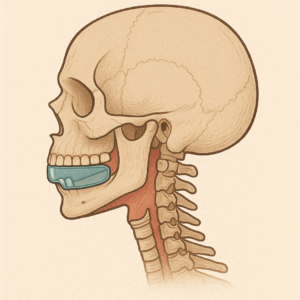

ガイコツさんがいますが、マイオブレイスを噛んでもらうと

(AI作成)

(AI作成)

こんな感じになりますが

(AI作成)

(AI作成)

当然ながら厚みがあると下顎骨は後方に向かって回転してしまいますね。。。。